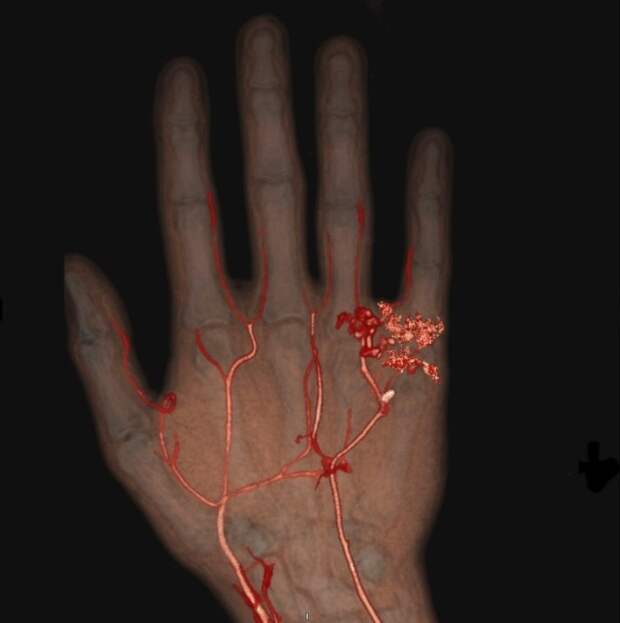

7. Артерии и вены